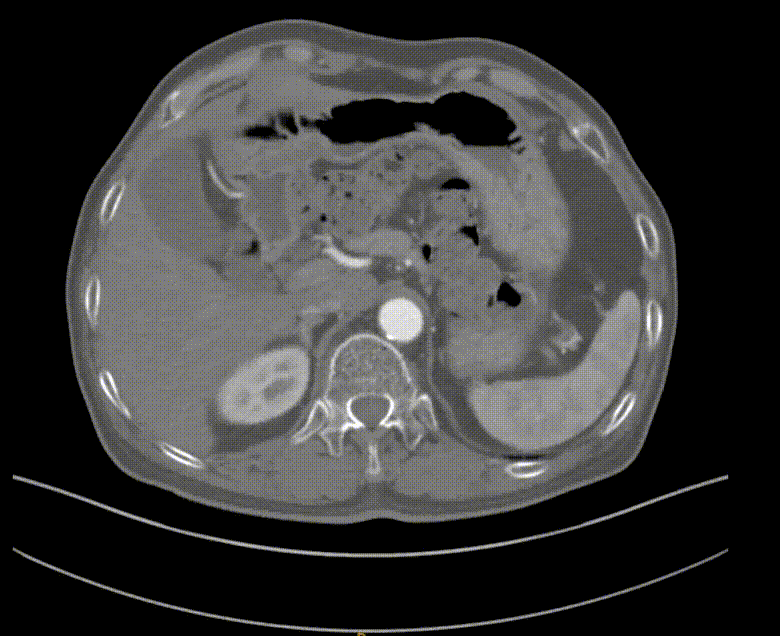

CTA:左侧股总动脉高钙化性偏心性严重狭窄病变,左股浅动脉及腘动脉全程弥漫性钙化病变,节段性狭窄,股浅动脉远段至腘动脉P1段完全闭塞,左侧胫前动脉至足背动脉闭塞

根据PACSS 透视/DSA下钙化分级属于PACSS Grade 4C

图为:血管准备:股浅旋切后球囊全程节段逐级式扩张

图为:评估血管准备:闭塞段残余狭窄90% ELUVIA全覆盖该区域病变